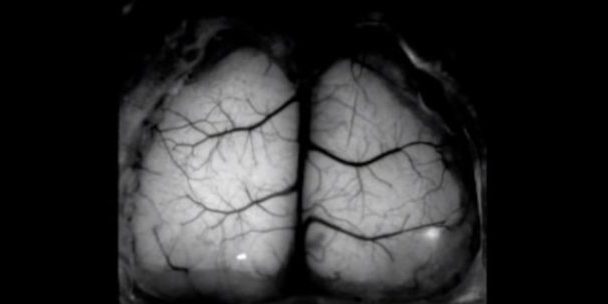

После этого грызунам провели хирургическую операцию, в ходе которой была удалена верхняя часть настоящего черепа мышей. Ее ученые заменили прозрачным имплантатом. Такая манипуляция позволила исследователям наблюдать за мозговой активность животных и получать изображения всего органа в режиме реального времени.

Как указывают авторы разработки, имплантат не был отвергнут иммунной системой грызунов, что позволяет проводить длительные наблюдения за их мозгом.